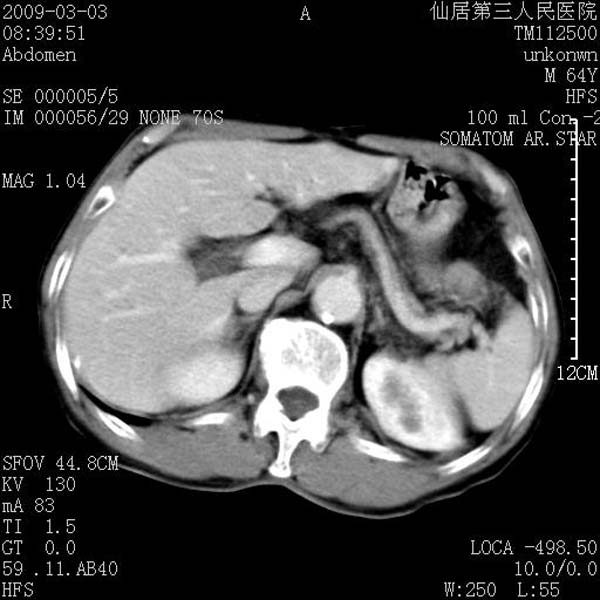

标题: CT18469:男性,64y,体检B超示肝脏低回声肿块,有胃溃疡手术 [打印本页]

患者,男性,64y,体检b超示肝脏低回声肿块,有胃溃疡手术史。

考虑----胃肠道间质瘤可能性大

考虑胃间质瘤可能性大。

胃肠道间质瘤!

ct值呢?感觉没强化,象囊性。

考虑肝囊肿并出血可能性大.

考虑高密度囊肿可能性大